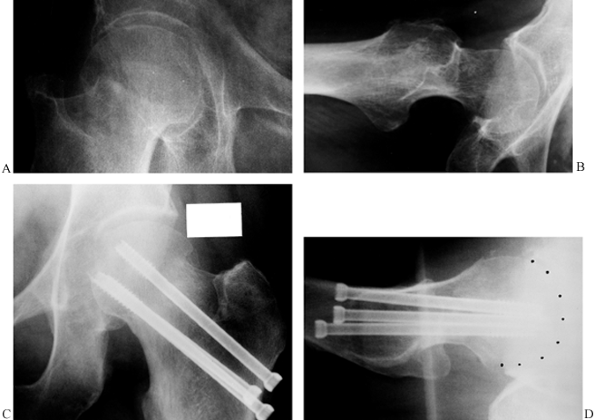

![]() |

Figure 19.5. Percutaneous cannulated screw fixation of an impacted, Garden stage I, subcapital hip fracture. A: AP radiograph of the hip fracture prior to fixation. B: Lateral radiograph. C: AP radiograph after cannulated screw fixation. D: Lateral radiograph; ideally, the screws could be spread out somewhat more and be more parallel.

|

fractures, whether displaced or undisplaced, with internal fixation

rather than prosthetic replacement (Fig. 19.5, Fig. 19.6). Even in displaced fractures such as a Garden stage IV where treatment is delayed, good internal fixation in anatomic